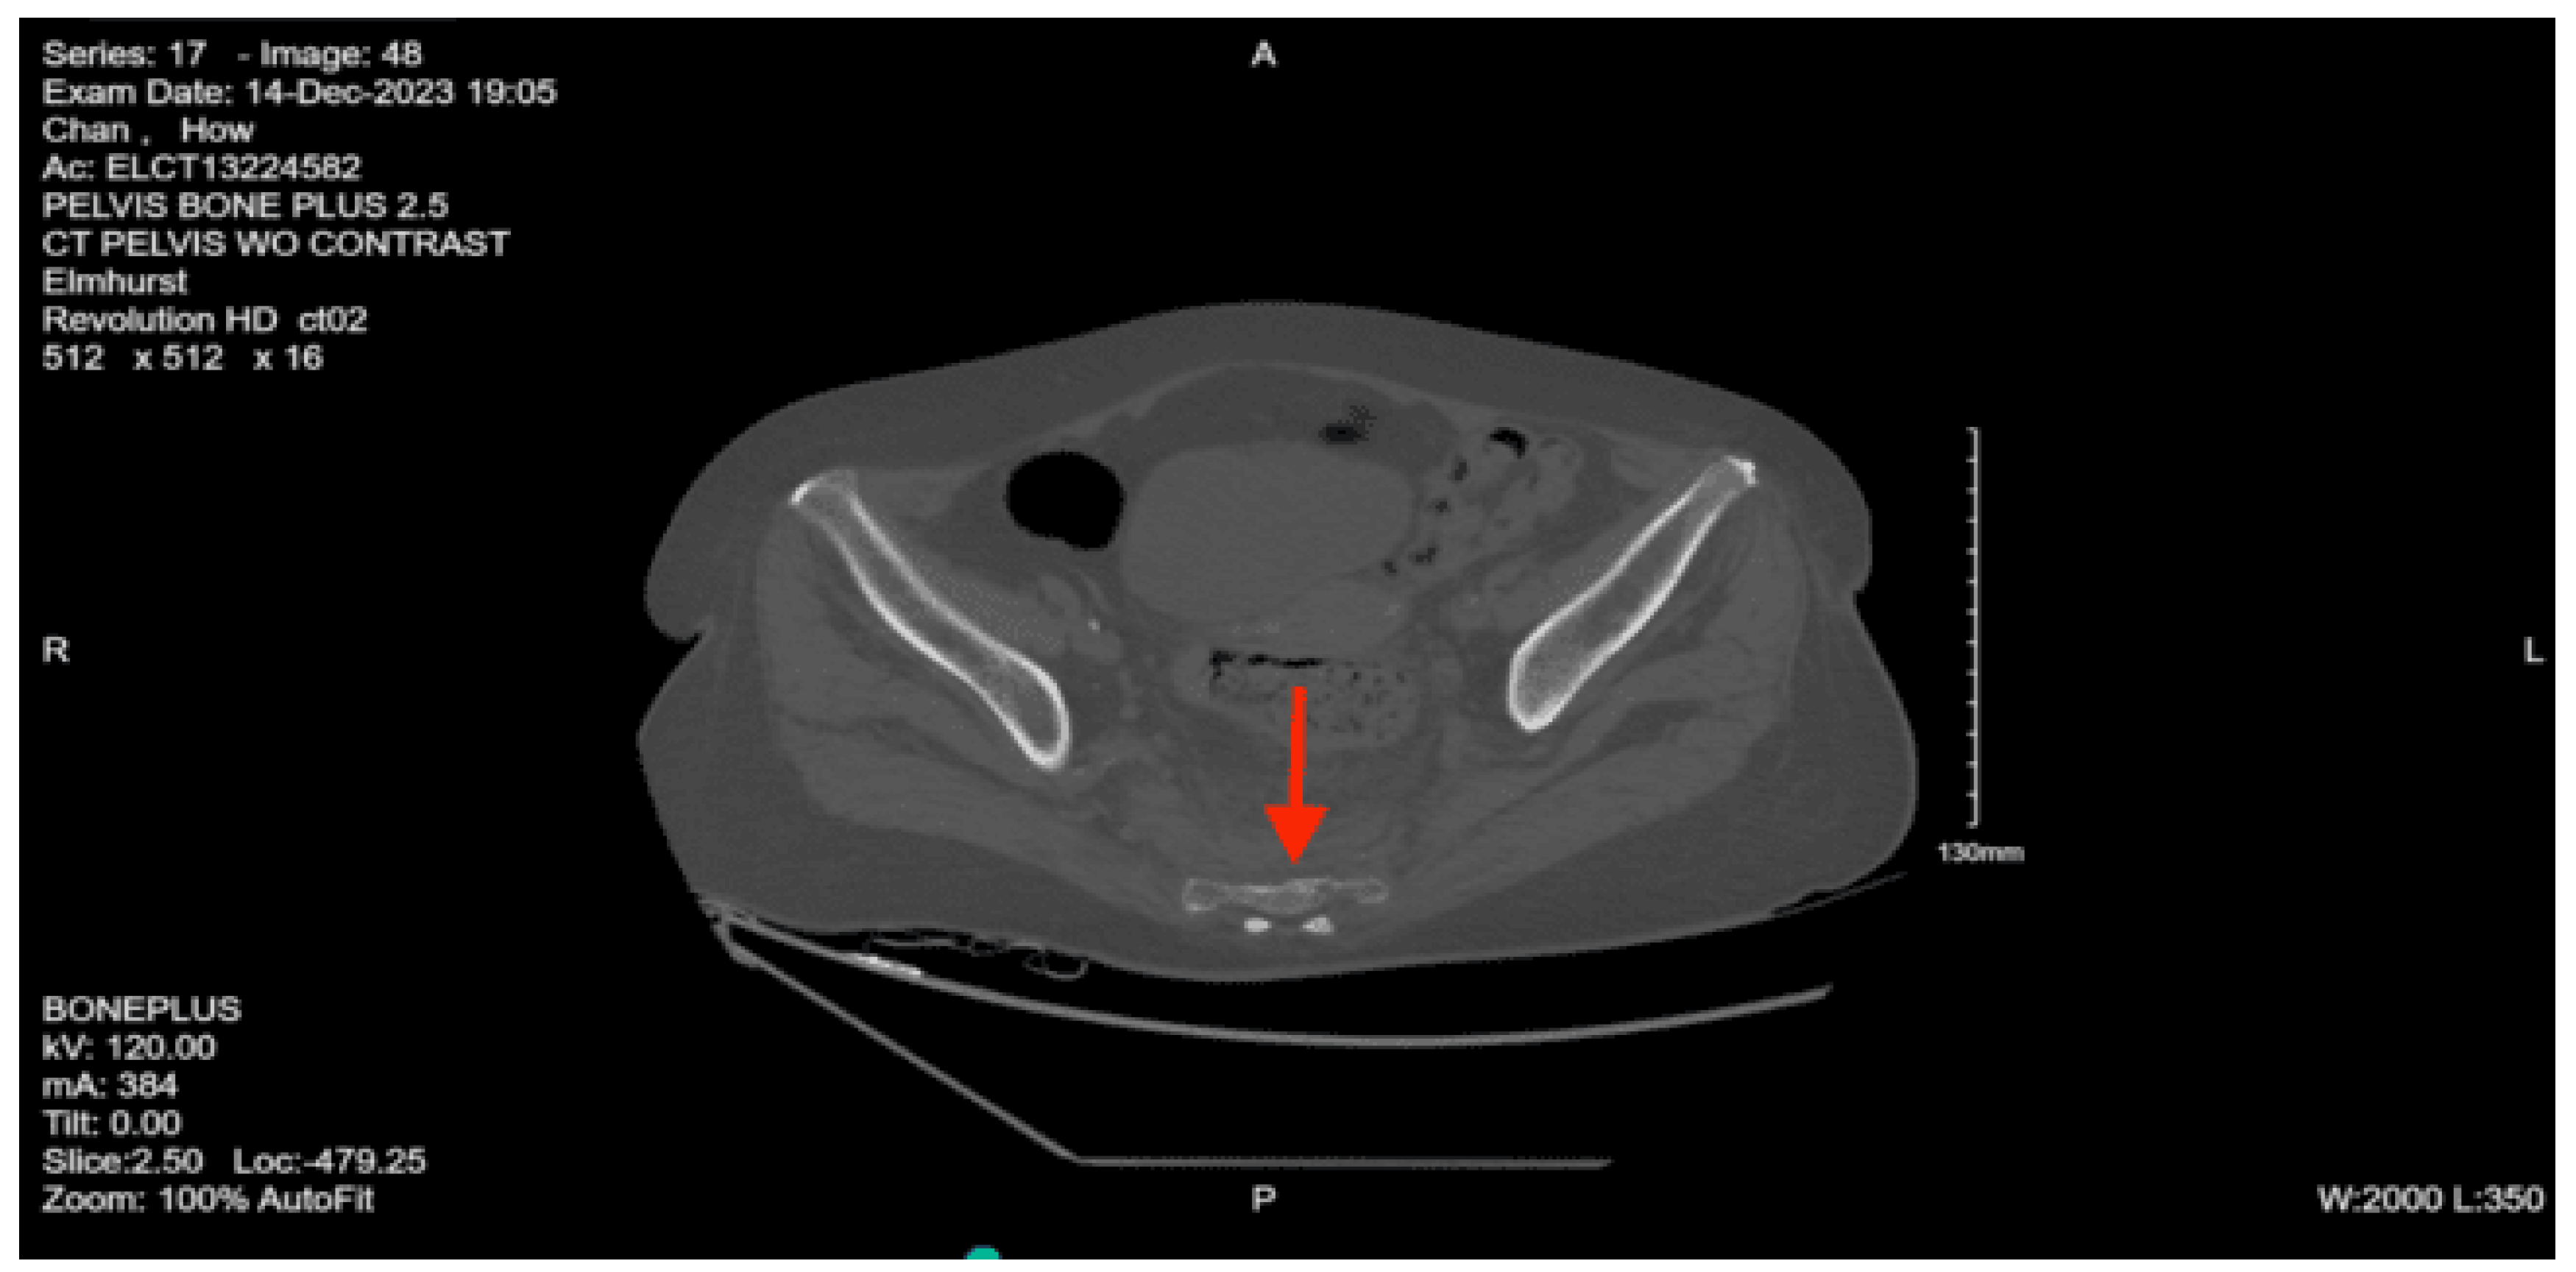

CT pelvis w/o contrast: Nondisplaced sacral fracture, approximately at the level of S4. Deformity at the sacrococcygeal junction, indeterminate chronicity. No other fractures identified. Diffuse osteopenia. Degenerative changes within the lower lumbar spine with grade 1 anterolisthesis of L4 over L5

XR shoulder right: no dislocation or acute displaced fracture identified